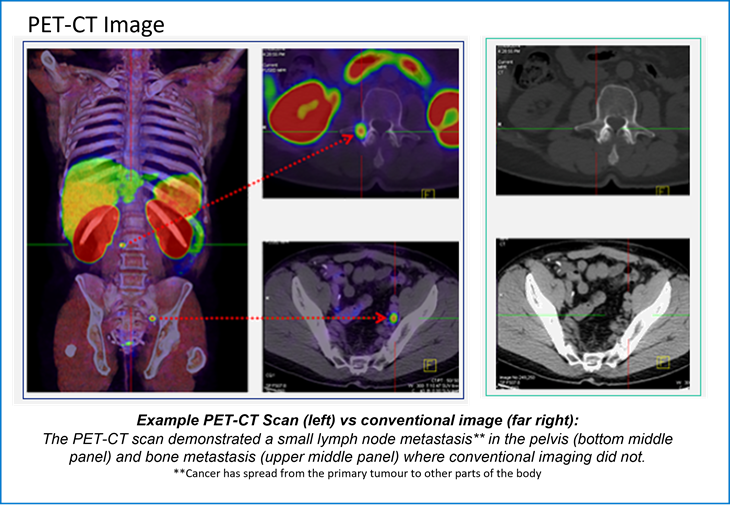

The PET-CT images

Positron emission tomography–computed tomography (PET-CT) is a global best practice diagnostic imaging tool that captures three-dimensional images of the body's biological functions. By utilising a small amount of a radiotracer (a radioactive substance that is used in medical imaging*), PET-CT scans can detect areas of abnormal metabolism or function in the body, including fast-growing cancers and infections.

PET-CT scans help doctors pinpoint the location of tumours or cancerous lesions, assess the extent of disease, determine whether lesions are benign or malignant, and identify any potential spread.